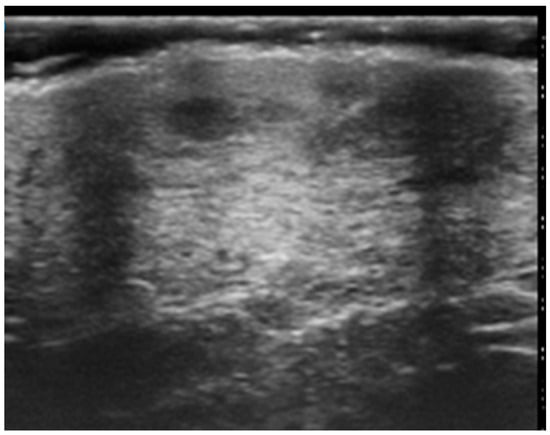

Figure 7. Diffuse infiltrative lesion (recurrence of B-cell lymphoma) examination performed with a very high-frequency ultrasound probe at 50 MHz in the region of the right scapula: Iso-hypoechoic lesions with nodular and multilobulated morphology and irregular margins infiltrating the epidermal and subepidermal tissue.

Cutaneous plaques were observed on HRUS as hypoechoic, diffusely infiltrative lesions (Figure 7).

Pseudonodular and nodular lesions were more frequently observed in B-cell lymphomas (70%), while diffusely infiltrative lesions were equally prevalent in both B-cell and T-cell lymphomas (50% each) (Figure 5).